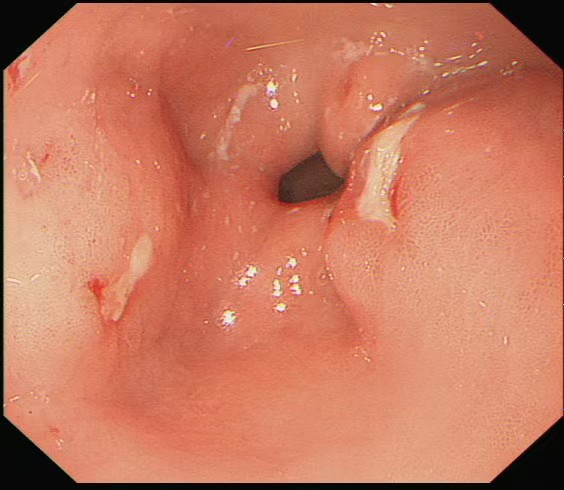

面对危急情况,高新生主任团队凭借丰富的临床经验和成熟的内镜技术,借助透明帽辅助清晰暴露视野,再用异物网篮精准抓取枣核,成功避开其锋利边缘,将这枚 “致命异物” 完整取出。随后,医生用钛夹如同 “内部缝合针”,牢牢封闭了溃疡创面。经过 5 天的住院观察,赵大娘腹痛症状明显缓解,复查结果正常后顺利出院。